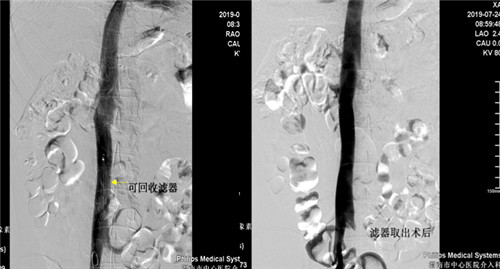

患者是一年轻男性,半年前因高血压性脑出血住院治疗,发现左下肢髂静脉股静脉腘静脉胫后胫前静脉血栓形成,由于脑出血有抗凝溶栓禁忌症,为预防肺栓塞的发生急诊行下腔静脉滤器(可回收)植入术,患者无脑出血后进行规范抗凝再无出血,超声复查下肢静脉血管未见新鲜血栓,D-二聚体正常,于7月24日早八点行经颈静脉下腔静脉滤器取出术,术后患者无腹痛发热出血等症状。

目前市中心医院对于下肢深静脉血栓形成患者常采用DENALI可回收下腔静脉滤器(最长回收时间窗632天)置入术预防肺栓塞的发生,该手术已在MILAN.COM广泛开展。但下腔静脉滤器取出术在渭南区域内尚未开展,市中心医院首次成功取出DENALI可回收下腔静脉滤器,标志着因担心滤器永久置入发生并发症而纠结放与不放的时代已结束,亦开创了渭南市血管介入新篇章,更好地为各科室的临床工作保驾护航,为更多的患者带来福音。